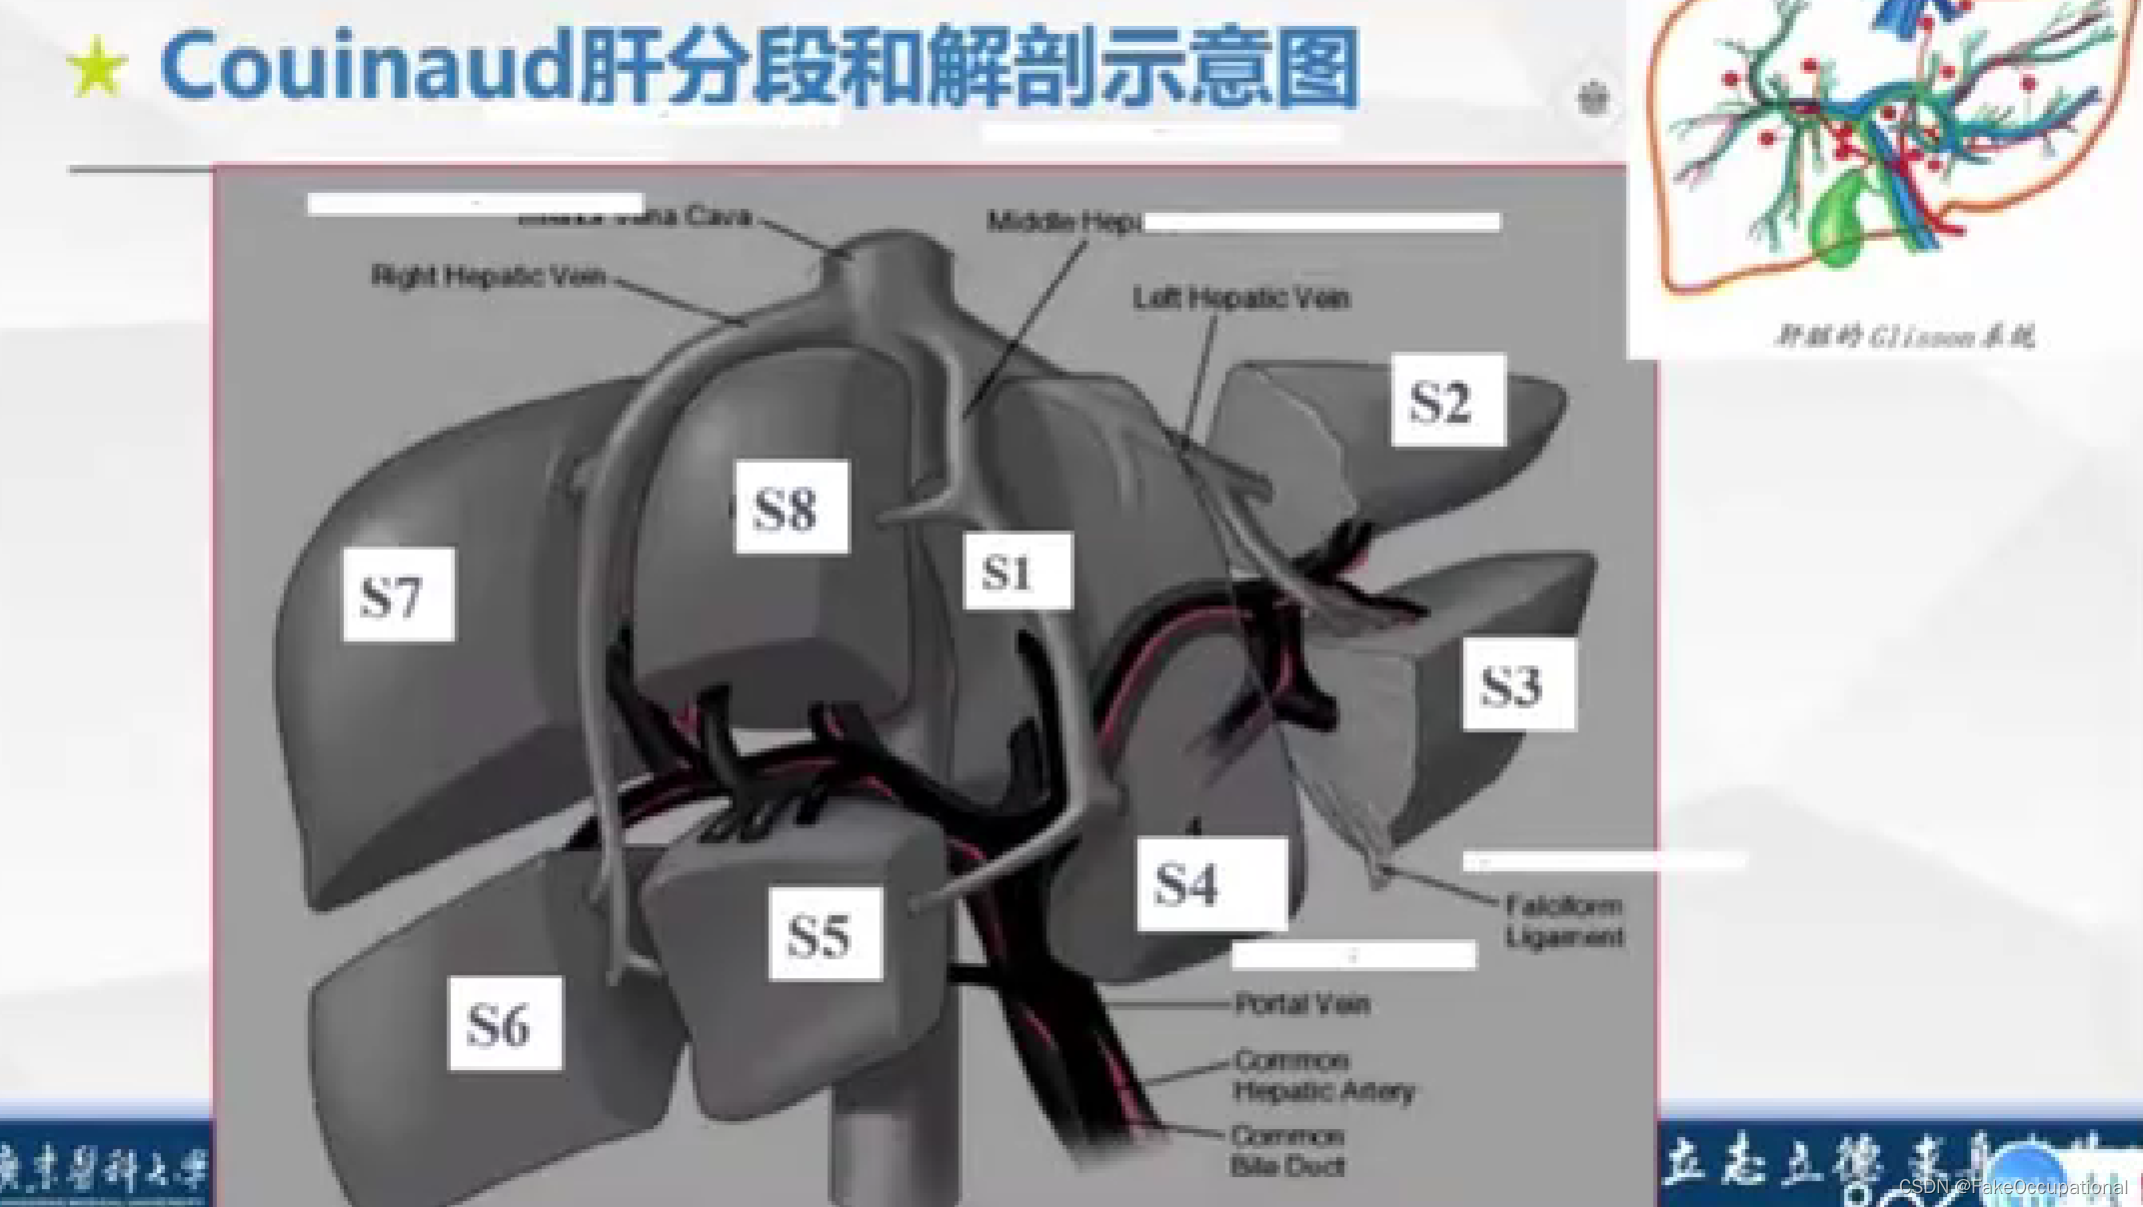

肝脏解剖概要

肝脏超声检查技术